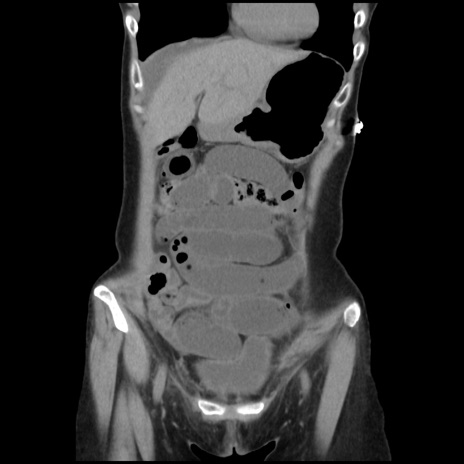

症例32(冠状断像)

【症例】40歳代 女性

【主訴】上腹部痛、嘔気・嘔吐

【現病歴】約9時間前頃から急に上腹部痛、嘔気、嘔吐が出現。改善しないため救急要請。

【既往歴】子宮頚癌(広汎子宮全摘術、放射線療法)、腸閉塞

【身体所見】腹部:平坦、軟、腸雑音亢進、上腹部を中心に腹部全体に圧痛あり。

【データ】WBC 8400、CRP 0.03